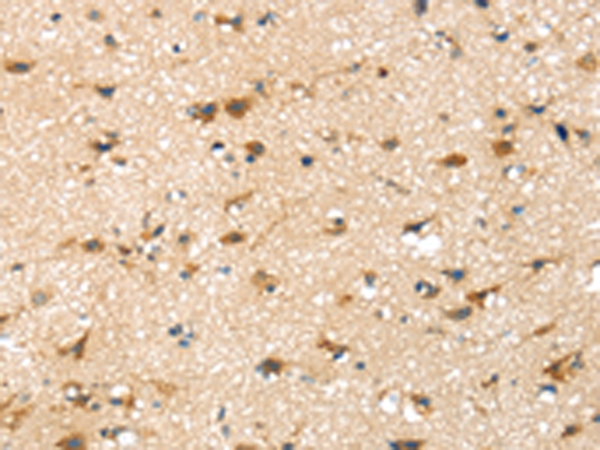

分类: 科研抗体货号: P00198别名: ASP2; BACE; HSPC104应用: WB,IHC反应种属: Human, Mouse, Rat